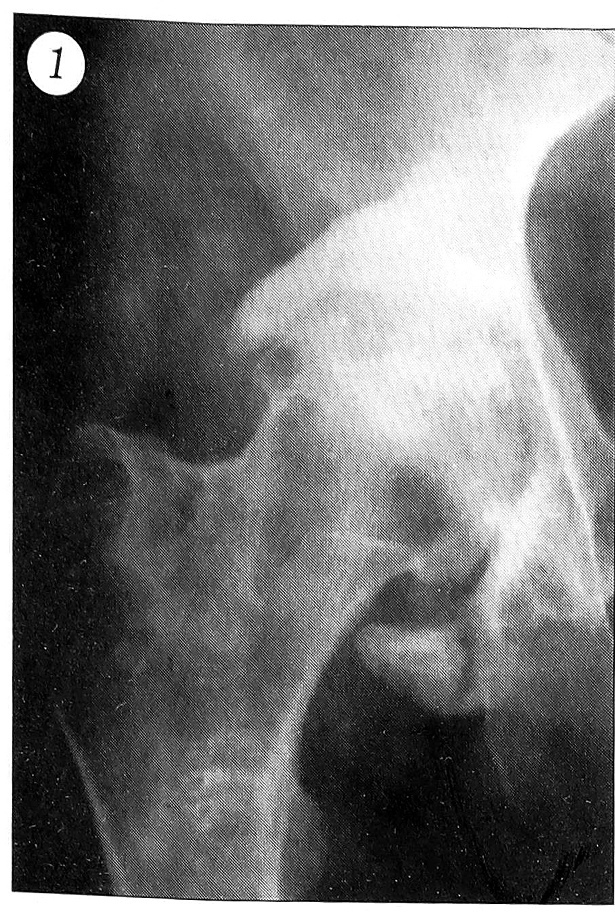

При компьютерной и магнитно-резонансной томографии обнаруживаются значительные дефекты суставной поверхности вертлужной впадины — от ее избыточных размеров (рис. 2) до фрагментации и смещения отломков. Определяются параартикулярные оссификаты, дополняющие картину протрузионного артроза тазобедренного сустава. Компьютерная томография дает возможность визуализировать состояние анатомических структур вертлужной впадины, их деформацию, пространственное расположение, величину диастаза между отломками, наличие дефекта в дне, направление и степень смещения крупных фрагментов, а также судить о массивности последних, что весьма важно для определения показаний к реконстмелкоочаговая оссификация, преимущественно по задней поверхности тазобедренного сустава. Наличие крупных обызвествлений ограничивает подвижность в суставе (причем в большей степени, чем инконгруэнтность), что сказывается на его статодинамической функции.

Рис. 2. Магнитно-резонансная томограмма левого тазобедренного сустава больного с посттравматической протрузией вертлужной впадины.